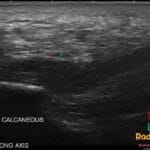

- Radiology Cases: Images with a to-the-point discussion highlighting the specific diagnostic criteria.

- Radiology Videos: Videos with a short description of learning points from them.

Latest Radiology Cases